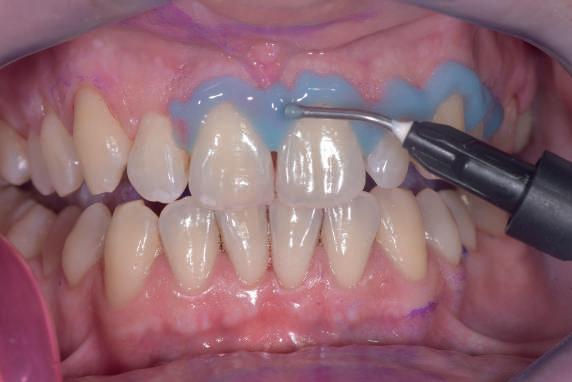

Si presenta alla nostra attenzione un paziente maschio, 35 anni, in apparente salute sistemica, fumatore, con la richiesta di controllare delle white spots, una leggera sensibilità e la richiesta di migliorare la luminosità del suo sorriso. Viene compilato e firmato il consenso informato. Il paziente viene motivato ad più efficace controllo del biofilm batterico e attraverso la condivisione dell’immagine clinica della topografia del biofilm batterico, (T.B.M.) scegliamo lo scovolino in gomma GUM Soft-picks (Sunstar) e lo sollecitiamo all’uso efficace degli spazi sovracrestali e allo spazzolamento in maniera delicata ma efficace della lingua. Sottoponiamo il paziente alla terapia parodontale non chirurgica con ablatore Comby touch (MECTRON) in modalità soft-mode per contenere la sua sensibilità. Valutiamo la sensibilità e modifichiamo i suoi stili di vita di igiene orale, di igiene alimentare e chiediamo di smettere di fumare. Il paziente riferisce di non essere disposto a rinunciare al fumo e chiediamo di ridurre il rischio di patologie e di discromie

da tabagismo passando all’uso dei dispositivi a tabacco riscaldato. Successivamente rileviamo il colore, con spettrofotometro, e con scala-colori Vita e documentiamo fotograficamente la condizione clinica presente.

Il colore rilevato è A2. Sottoponiamo il paziente ad uno sbiancamento pro-

fessionale con un principio attivo PAP (acido ftalimidoperossicaproico) che presenta il vantaggio di non sollecitare la sensibilità, pur mantenendo l’aspettativa di un risultato efficace nell’ottenere la luminosità del sorriso. Lo sbiancante ad uso professionale BRILLIANT LUMINA (Coltene), risulta essere per l’operatore di facile applicazione: ven-

gono protette le gengive con la diga liquida fotopolimerizzata, e si mescola il gel sbiancante lasciando cadere nel vasetto contenente 2 ml di gel, 3 gocce di liquido attivatore. Si ottiene il gel sbiancante di una consistenza ideale per una applicazione sulle superfici dentali sicura e pratica durante l’apposizione. Vengono eseguiti 4 step da 15 minuti.

Dopo ogni step viene aspirato il gel, pulite le superfici dentali con del cotone idrofilo e si riappone nuovamente il gel. Al termine dei 4 step, si aspira, si asciuga e viene tolta la diga. Si rileva e si condivide con il paziente il risultato ottenuto, A1, e viene documentato fotograficamente. Il paziente appare gioioso del risultato è favorevolmente colpito di non aver sofferto durante il trattamento di sensibilità. Alla persona assistita sono stati programmati dei follow-up per il trattamento successivo delle white spots con applicazioni di resine infiltranti e rigenerazione guidata dello smalto.